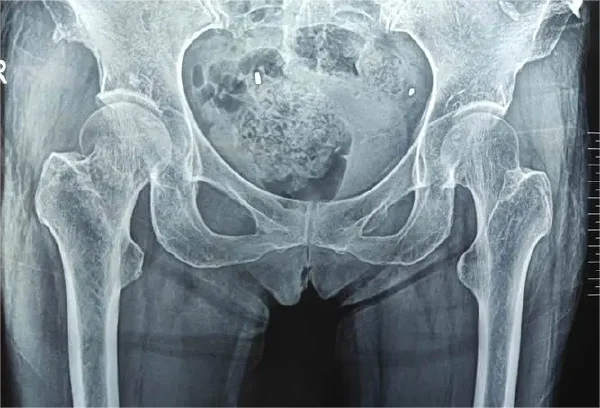

诊断股骨骨折需要结合临床信息、辅助检查结果及医生经验做出判断。文献指出,影像学检查如X线和CT扫描是确诊的主要手段。通常情况下,当患者出现因外伤导致的股骨剧烈疼痛、肿胀、畸形及功能障碍时,需要立即进行初步检查。医生会通过体格检查来评估损伤的程度和类型,其中包括检查肢体的长度、轴线以及活动范围。

X线检查是诊断股骨骨折的首选影像学手段,可以明确骨折的形态、部位及移位程度。CT扫描则用于对复杂骨折进行进一步详细评估,特别是在需要手术治疗的情况下,精准了解骨折情况有助于制定更准确的手术方案。